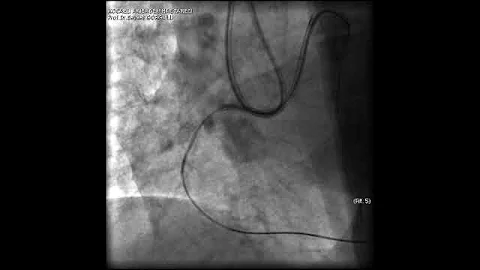

Aortic Dissection And Radial Rupture During Retrograde Cto Pci: Management Of Complications Vİdeo 25